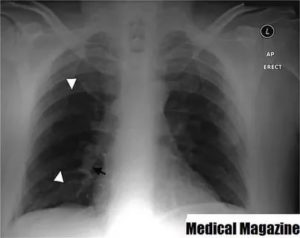

Основным признаком спаечного процесса на легком является наличие тени, которая появилась на снимке. Стоит учесть тот факт, что она никак не изменяет свою форму при вдохе и выдохе. Наряду с этим легочное поле будет менее прозрачным, а диафрагма и грудная клетка могут быть несколько деформированы. Зачастую спайки наблюдаются внизу легкого.

Достоверная визуальная диагностика плевральных шварт возможна только если соединительно-тканные образования больше 1 см в толщину. В противном случае тень от спаек накладывается на ткань легкого и не видна на рентгенограмме. При указании на характерные жалобы, которые возникли и сохраняются после перенесенного плеврита, требуется проведение дополнительных исследований таких, как:

Для обнаружения легочных заболеваний в первую очередь используется флюорография. Эту процедуру необходимо проводить ежегодно, в основном она направлена на выявление ранней стадии туберкулеза. Однако опытный рентгенолог может выявить на снимке образовавшиеся плевральные спайки, которые выглядят тенями. Причем форма их не меняется в зависимости от вдоха и выдоха.

При необходимости дополнительно назначается рентген. Как правило, спайки располагаются в нижней части легкого. При этом будет более темная картинка, а также может быть частичная деформация грудной клетки и диафрагмы.

Основной атрибут, указывающий на спайку справа, является тень, видная на Rg-снимке. При этом затемнение не изменяется при вдохе и выдохе пациента. Одновременно снижается прозрачность легочной поверхности.

В тяжелых случаях наблюдается деформирование грудной клетки и диафрагмальной области. При таком состоянии диафрагма ограничивает свою подвижность. Чаще всего такие спайки расположены в нижних отделах легкого.

Распознать спайку по снимкам можно, если на нем легкие мутные, а еще при сравнении фотографий на вдохе и на выдохе. Спайка выглядит как тень, положение которой не меняется во время дыхания. Иногда наблюдается изменение формы и ограничение подвижности диафрагмы и грудной клетки.

Чаще всего спайки обнаруживают в нижней части легких.